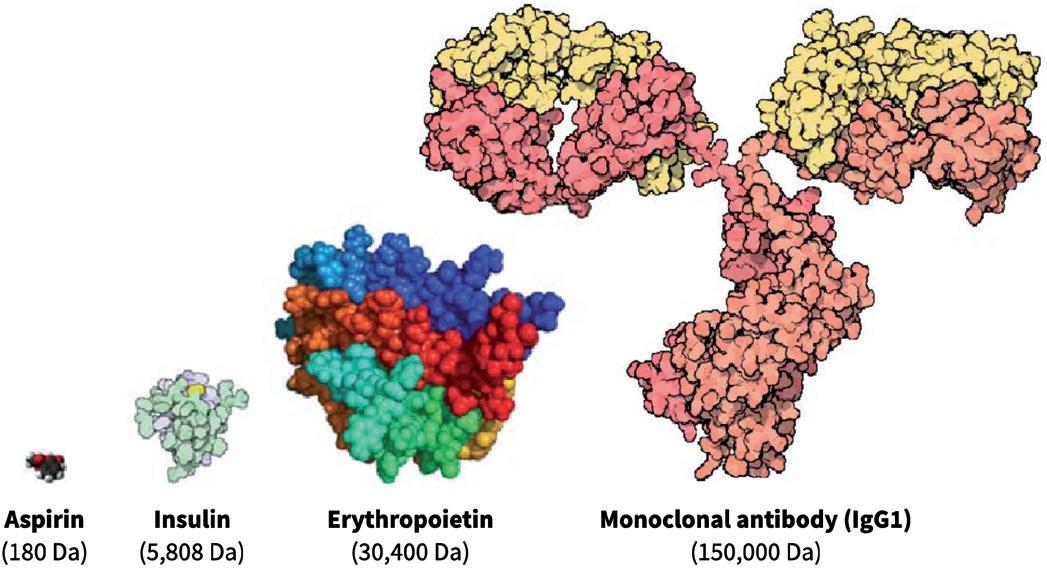

Generally, biologics are therapeutic proteins derived from living systems (such as bacteria, yeast, plants or animals) or blood that differ from “small molecules”, which are synthetic, or plant derived (see Figure 1). Examples of biologics include vaccines, growth factors, monoclonal antibodies and immune modulators. With their high target specificity and comparatively low toxicity, biologics are one of the fastest-growing therapeutic classes in the pharmaceutical industry.

Figure 1: Comparison of three different classes of biologic drugs with a typical small molecule. (Adaptation from Revers L & Furczon E, Canadian Pharmacists Journal, 2010.)